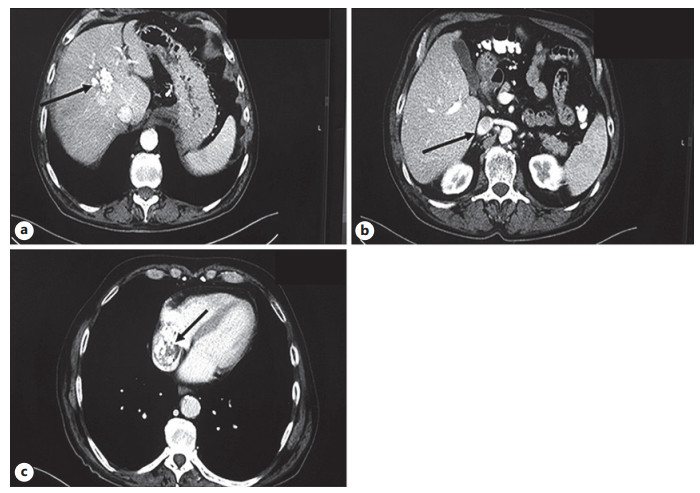

Abstract: Hepatocellular carcinoma (HCC) is considered to be the fourth most frequent cause of cancer-associated death globally. HCC might be associated, especially in advanced stages, with the formation of tumor thrombus (TT), which can be located in the portal vein, as well as in hepatic and/or inferior vena cava (IVC) veins. Nevertheless, the extension of TT to the right atrium (RA) is infrequent with an unfavorable prognosis. We present a rare case of a male patient with HCC and IVC TT extending to the RA. The atrial thrombus was the first manifestation of HCC diagnosed by cardiac ultrasound. So far, the patient has undergone 4 courses of transarterial chemoembolization in combination with systemic therapy with sorafenib, and under this therapeutic approach long-term survival has been achieved.